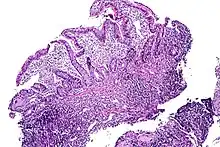

| Tissue of the ileum with inflammatory changes due to Crohn's disease | |

Crohn's disease – also known as regional enteritis, it can occur along any surface of the gastrointestinal tract. The most common location for Crohn's disease to manifest, with or without the involvement of the colon or other parts of the GI tract, is in the terminal ileum (the final segment of the small intestine).[5] In 40% of cases, it is limited to the small intestine.[6]